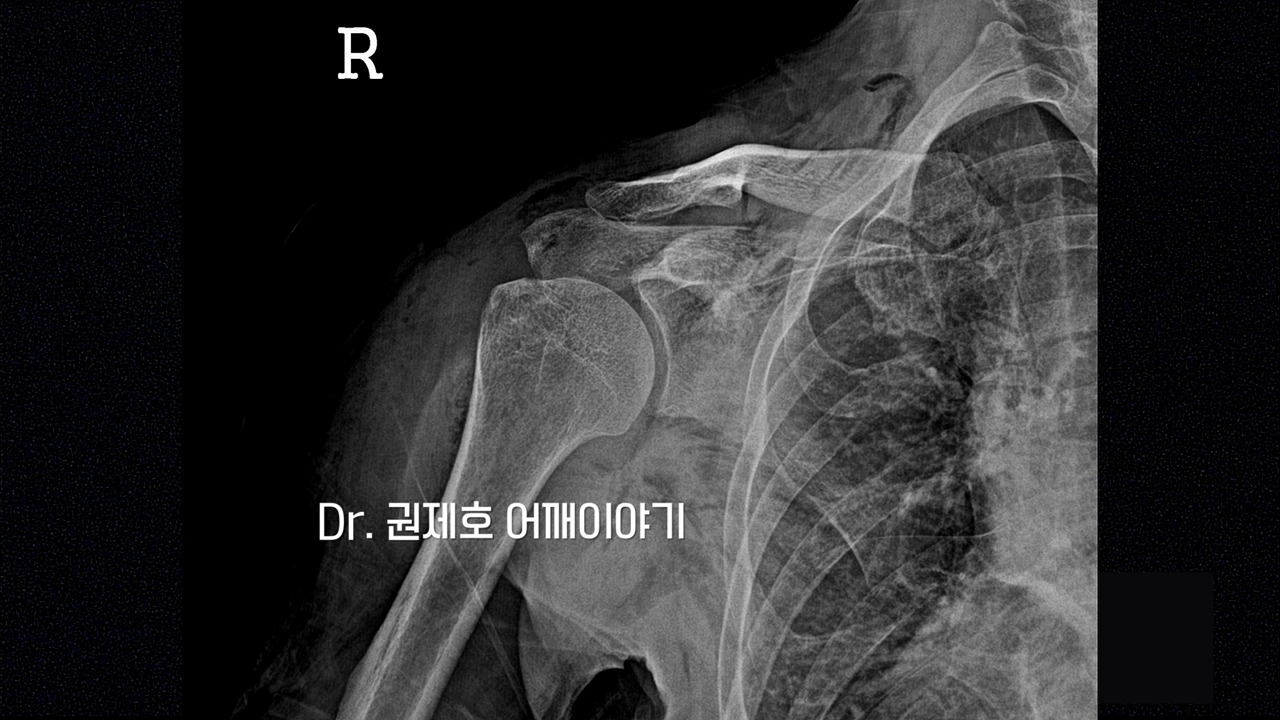

진료를 보신 분은 아시겠지만 가장 기본적인 검사는 방사선 사진입니다. 검사에서 보면 견봉이라는 뼈 끝에 뼈가 자라난 것이 보입니다. 저렇게 원래의 뼈가 아닌 세월의 흔적으로 자라난 뼈를 골극이라고 표현한다. 간혹 뼈가 다친 것이 아닌데 왜 검사를 하느냐 하시는 분들이 있다. 뼈가 다치지 않아도 이러한 변형이 나타나기 때문에 본다고 생각하면 될 것 같습니다.